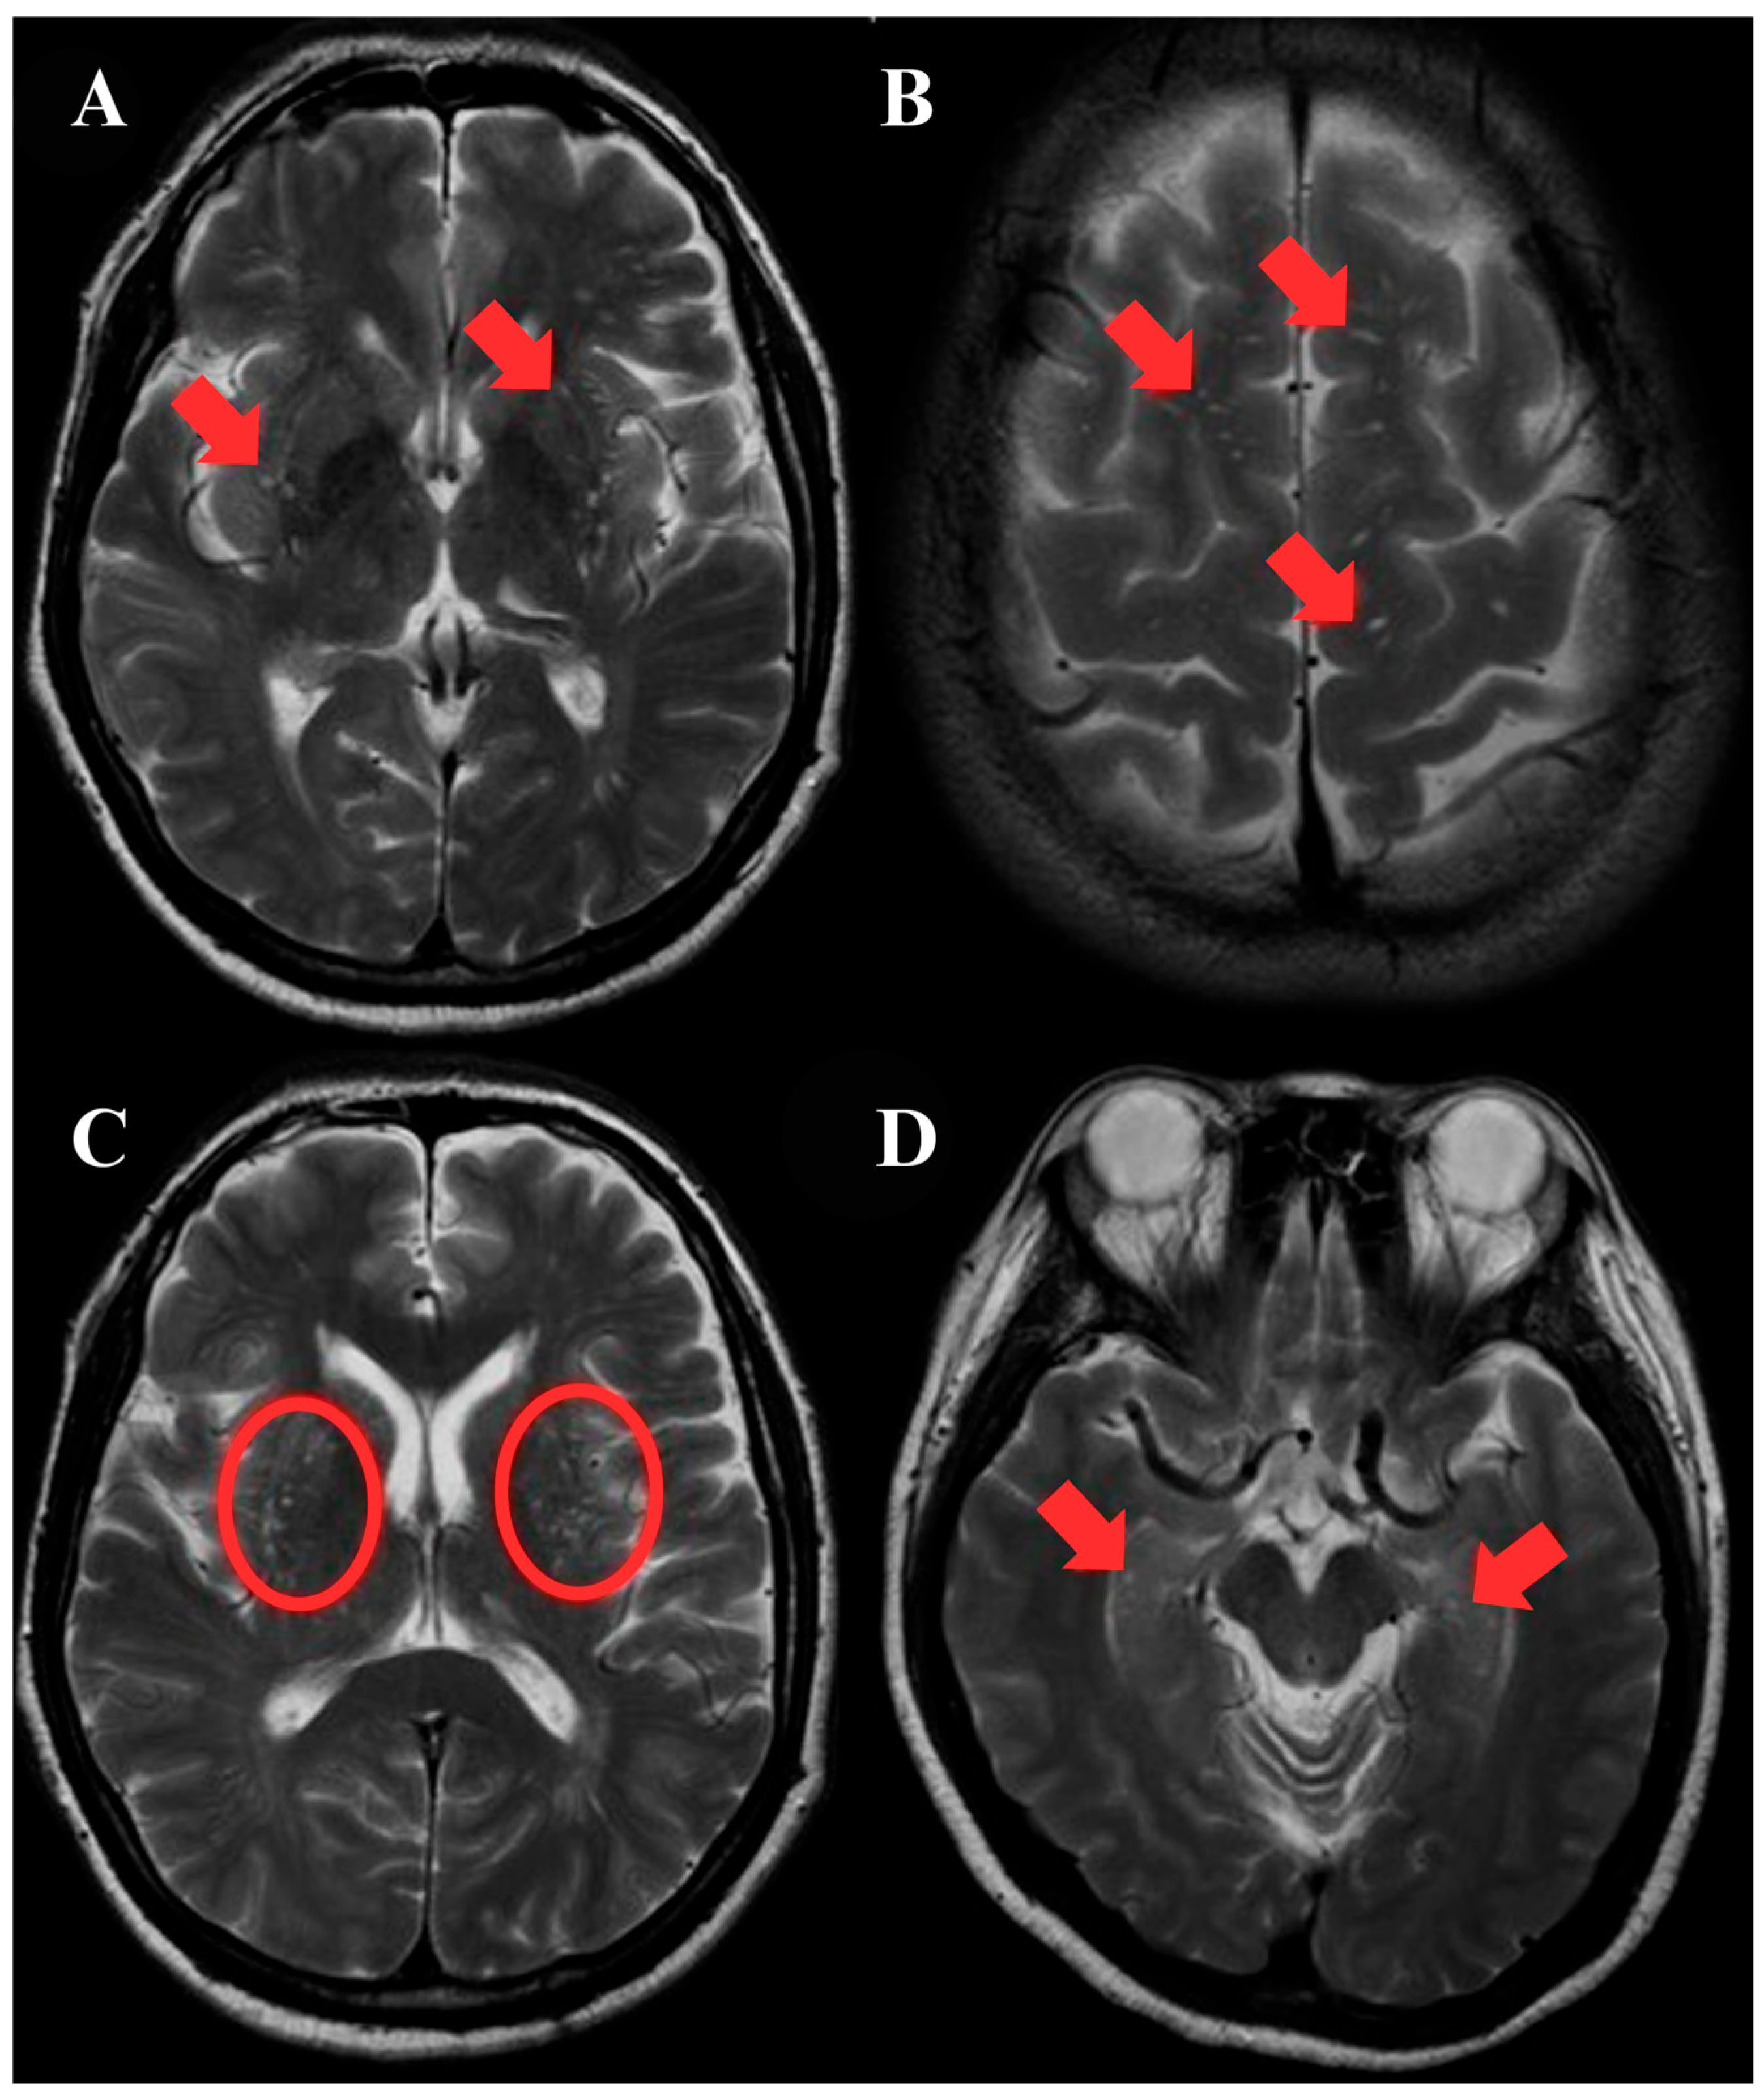

2.5. ePVS Identification and Scoring

3.2. ePVS